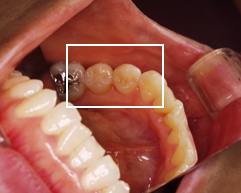

治療前

他医院にて虫歯部分を削り、金属の詰め物をしていた部分の金属をはずしている状態

院長の吉本の診断は以下でした

虫歯治療による2次齲触(虫歯治療した部分に再度バイキンが入り込み、また虫歯になっている状態)